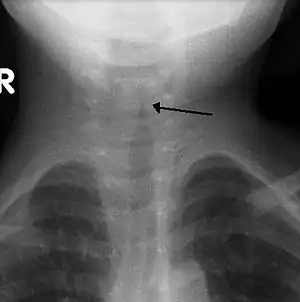

![]() Рентгенологічна ознака крупу у дитини — видно тінь по ходу дихальних шляхів у вигляді «шпилю» верхівкою вверх. Рентгенологічна ознака крупу у дитини — видно тінь по ходу дихальних шляхів у вигляді «шпилю» верхівкою вверх. | |

Зазвичай рентгенографію не проводять, проте, якщо це обстеження було зроблено, воно показує так зване шпилеподібне звуження трахеї, назване так через схожість з шпилем будівлі. Але у половині випадків цю ознаку не виявляють.[9] Ларингоскопію проводять при підозрі на справжній круп і вкрай рідко при несправжньому, тільки тоді, коли існують нерозв'язані протиріччя у клінічних проявах.